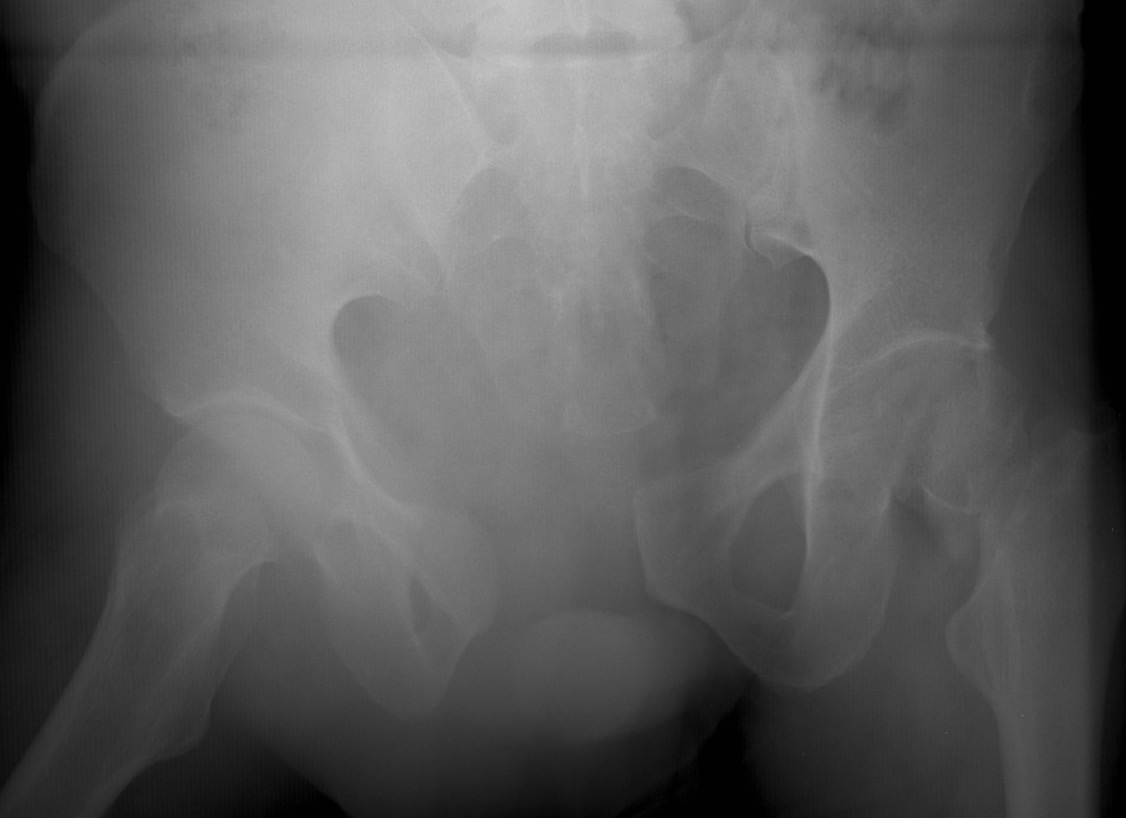

APC pre binderAPC post binder

APC fracture pre- and post binder (note improper position cranial to trochanters)